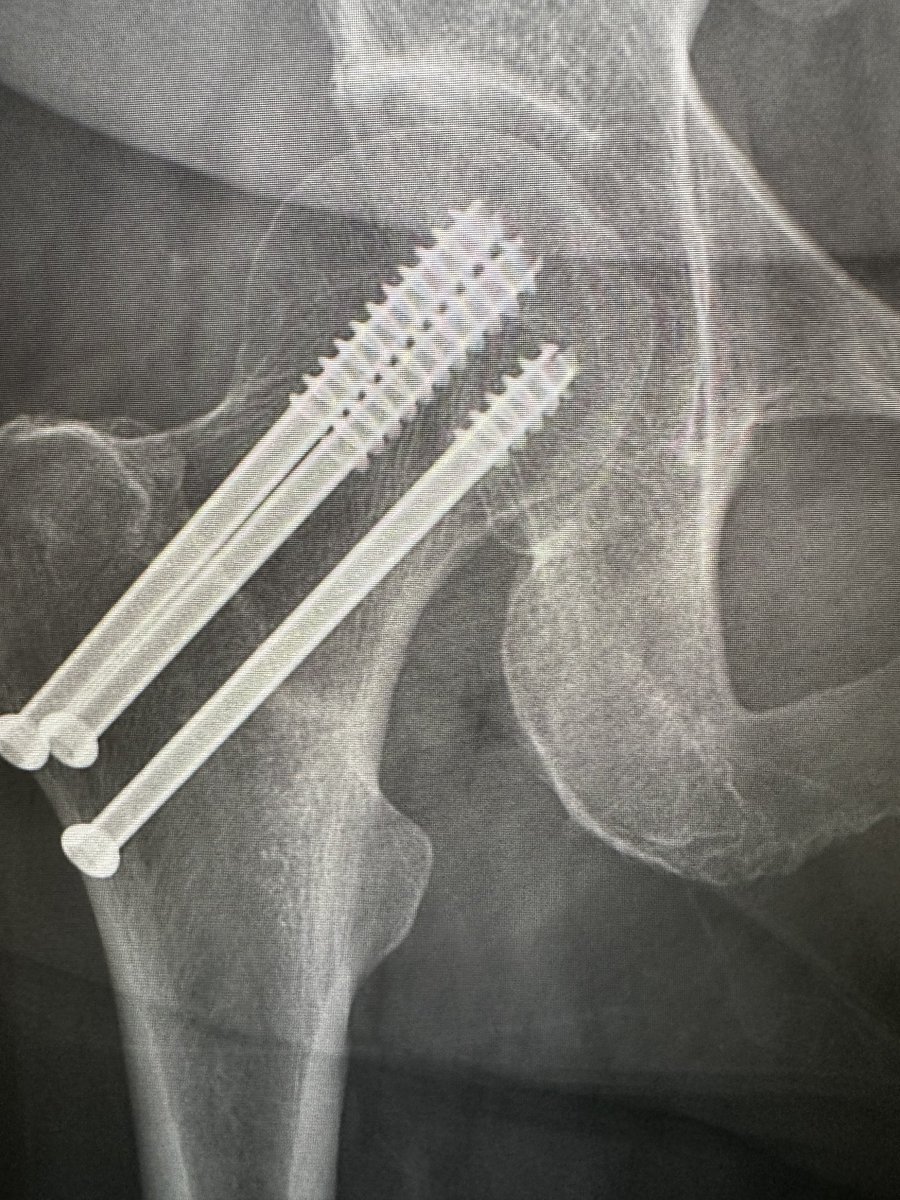

Female 67 y/o - THA

*Approach?

*What stem do you choose?

*Comments & tricks?

@AAHKS_YAG @AAHKS_YAG @JArthroplasty @AAOS1 @CleClinicArthGp